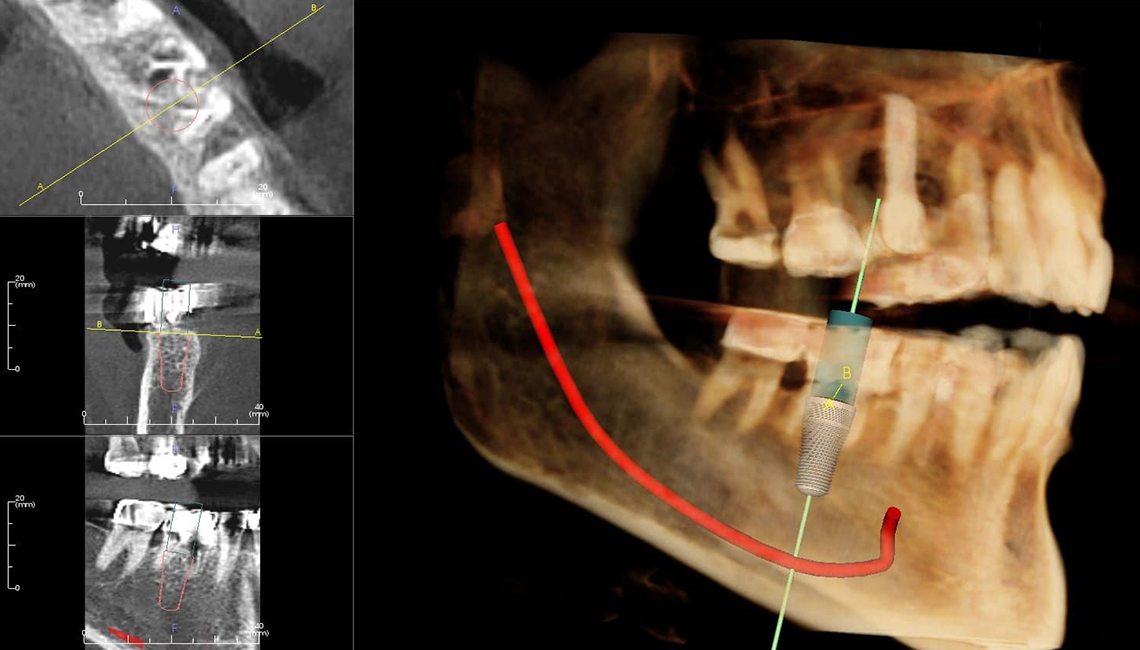

დენტალური იმპლანტაცია არის ტიტანის ხრახნის ჩასმა ყბის ძვალში, კბილის ფესვის ნაცვლად. იმპლანტით შესაძლებელია დაკარგული კბილების აღდგენა, ბუნებრივი ვიზუალითა და ფუნქციით. დენტალური იმპლანტი საუკეთესო ალტერნატივაა ხიდებისა და პროთეზის. დენტალური იმპლანტაციის ოპერაცია ტარდება რამდენიმე ეტაპად. შუალედებში რეაბილიტაციისა და შეხორცების პროცესებით. იმპლანტაციის პროცედურა მოიცავს:

1. პირის ღრუს მოწესრიგებას (დაზიანებული კბილის ამოღებას)

2. საჭიროების შემთხვევაში ძვლის დამატება

3. იმპლანტაცია

4. შეხორცება

5. საყრდენის განთავსება

6. გვირგვინის გაკეთება